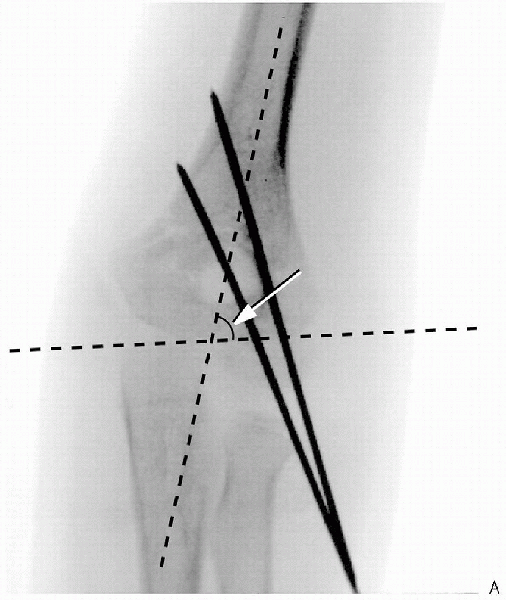

FIGURE 12-4. A: Two lateral pins used to obtain fixation for supracondylar humerus fracture. Note divergence of pins and Baumann’s angle (arrow).

FIGURE 12-4. (Continued) B: Note lateral reduction of fracture on lateral film. Note anterohumeral line and relationship with capitellum (arrow). C: Anterior humeral line falling in front of capitellum (left elbow).

pins should be slightly convergent proximal to distal (Fig. 12-4). This